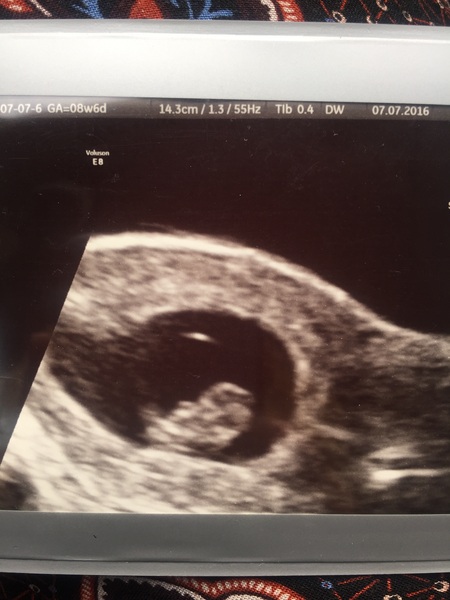

In other news... Baby measuring 8+5 (just one day behind what lmp suggests) with a healthy heartbeat. We also saw a little foot wiggle too GrinGrinGrin